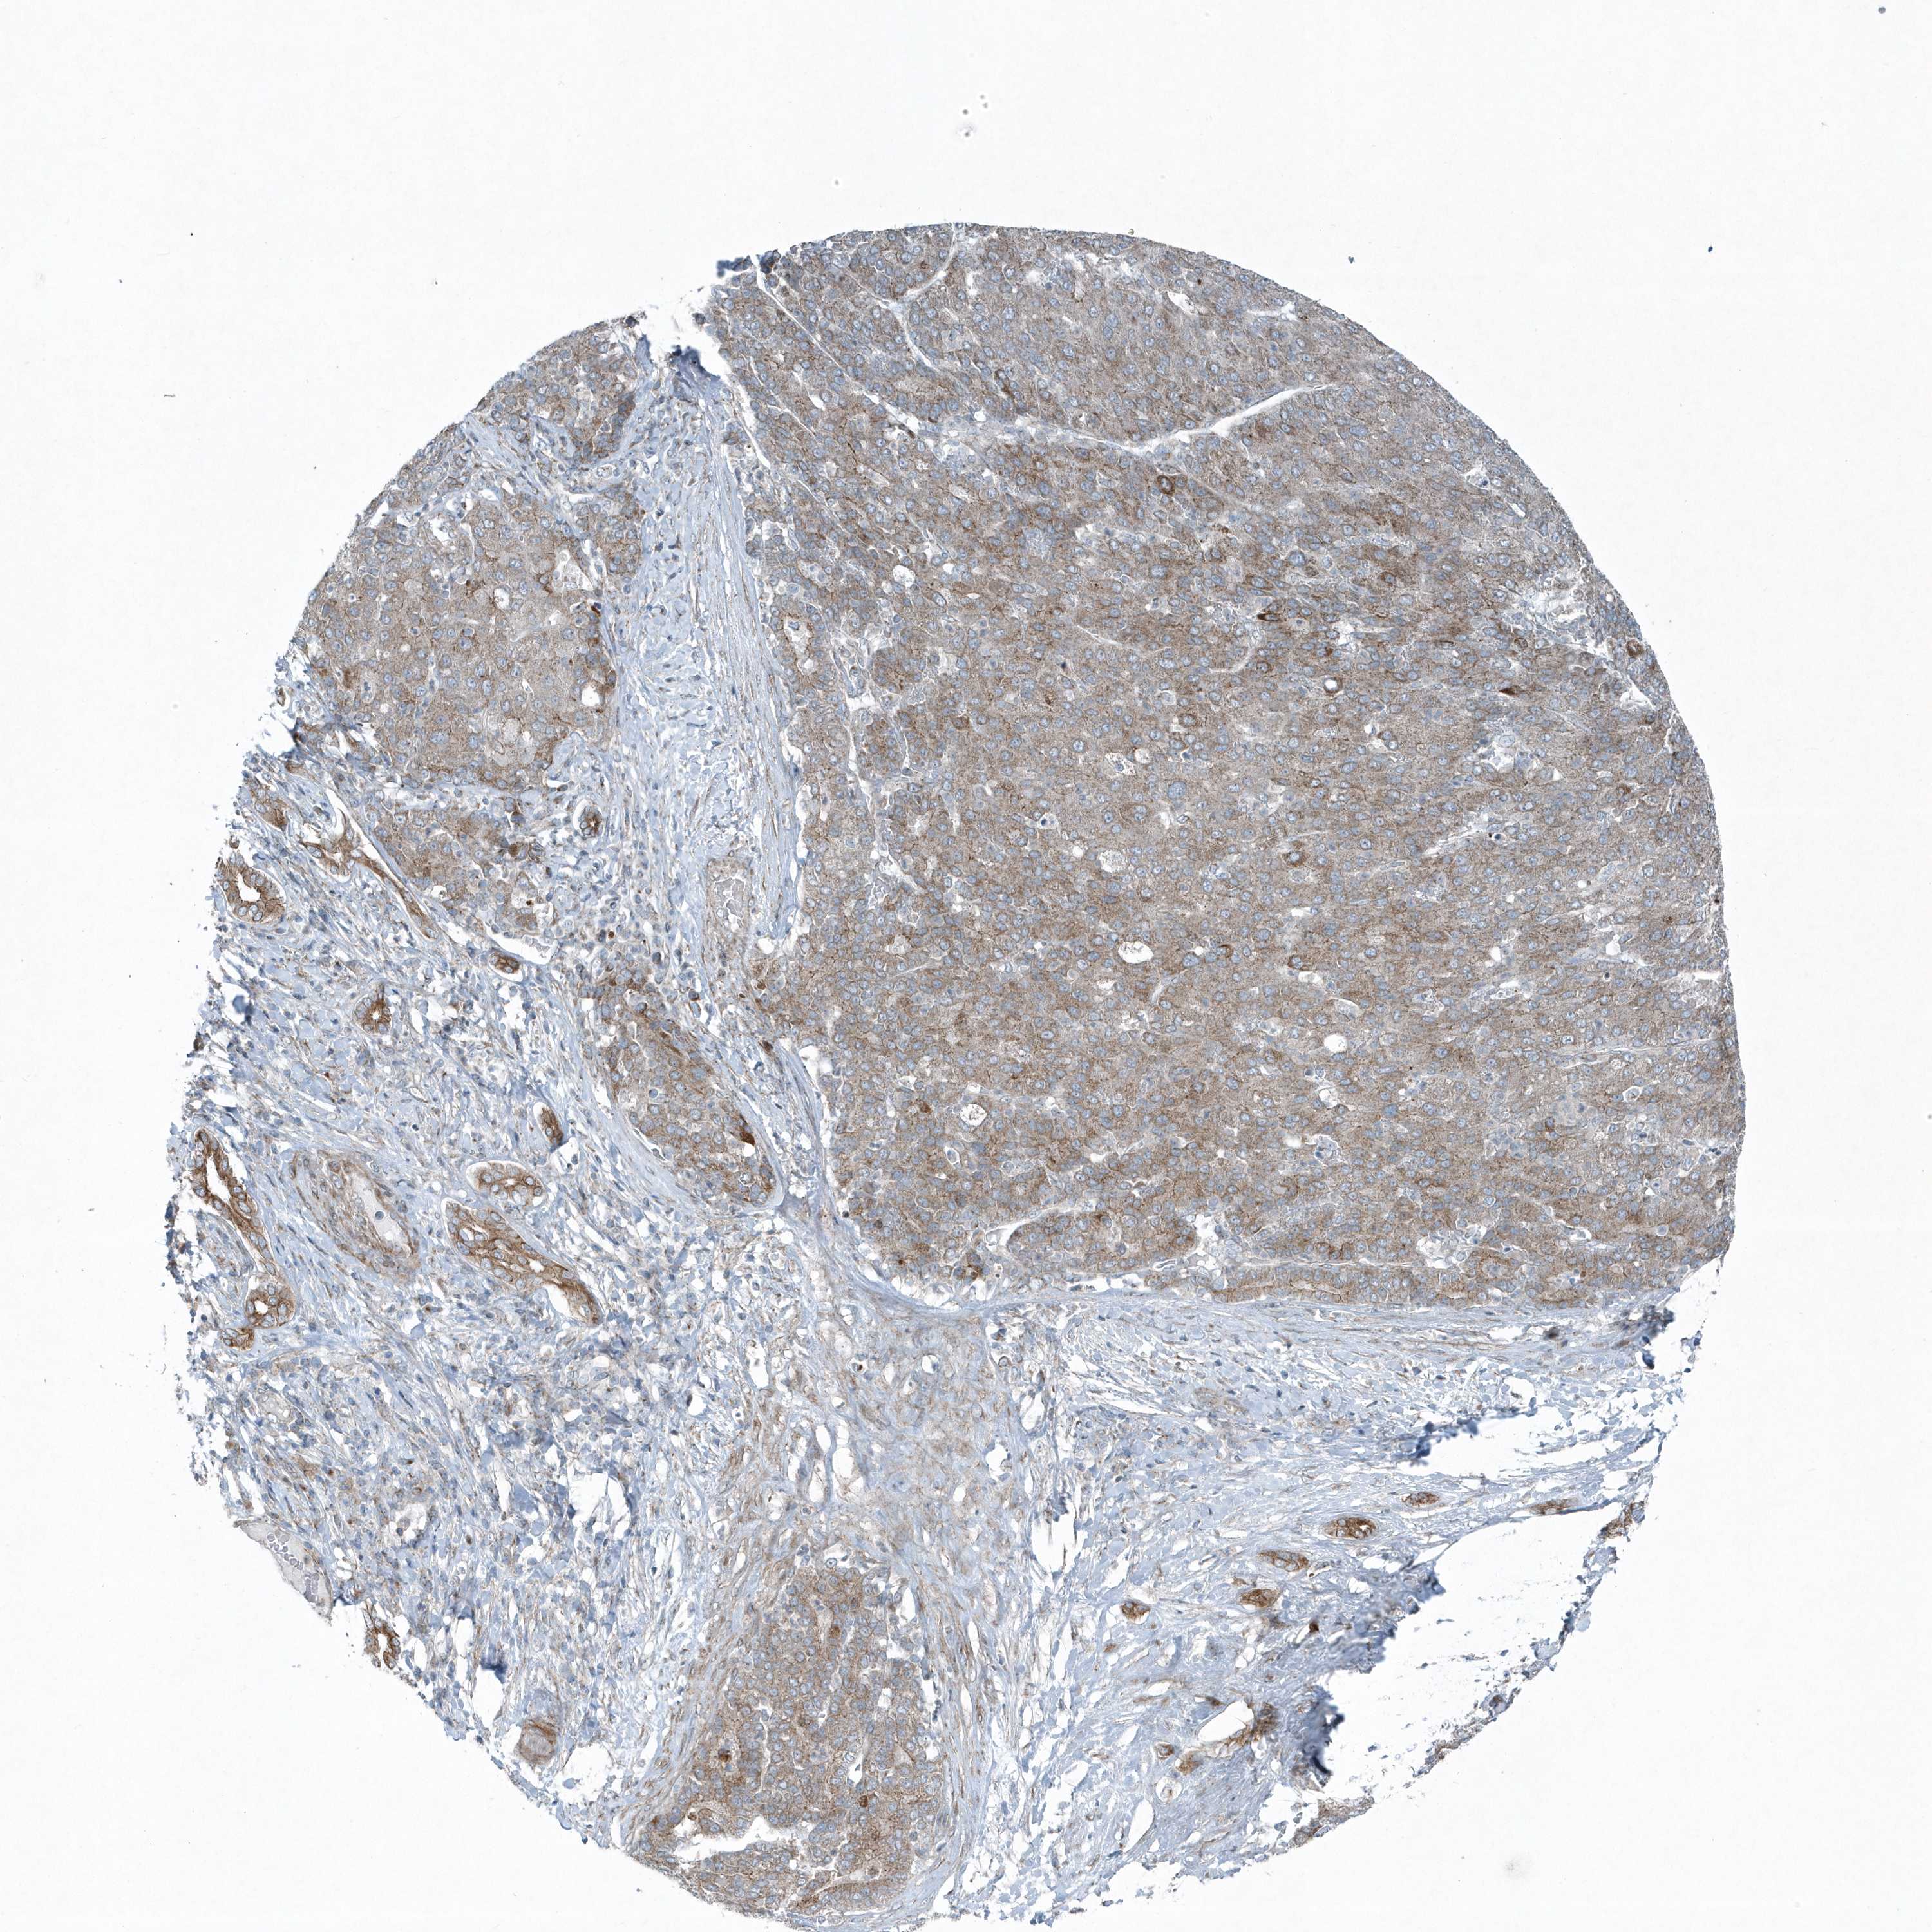

LIVER CANCER - Protein expressioni

A mouse-over function shows sample information and annotation data. Click on an image to view it in a full screen mode. Samples can be filtered based on level of antibody staining by selecting one or several of the following categories: high, medium, low and not detected. The assay and annotation is described here.

Note that samples used for immunohistochemistry by the Human Protein Atlas do not correspond to samples in the TCGA dataset.

Antibody stainingi

Antibody staining in the annotated cell types in the current human tissue is reported as not detected, low, medium, or high, based on conventional immunohistochemistry profiling in selected tissues. This score is based on the combination of the staining intensity and fraction of stained cells.

Each image is clickable and will lead to virtual microscopy that enables deeper exploration of all samples and also displays staining intensity scores, fraction scores and subcellular localization as well as patient and tissue information for each sample.

Antibody HPA035849

Antibody HPA035850

Staining

High

Medium

Low

Not detected

Intensity

Strong

Moderate

Weak

Negative

Quantity

>75%

75%-25%

<25%

None

Location

Nuclear

Cytoplasmic/membranous

Cytoplasmic/membranous,nuclear

Cholangiocarcinoma

Carcinoma, Hepatocellular, NOS